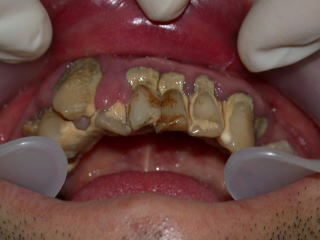

初診時平成17年8月

虫歯も歯石もひどく、歯肉は炎症を起こし、口腔内状態は劣悪でした。